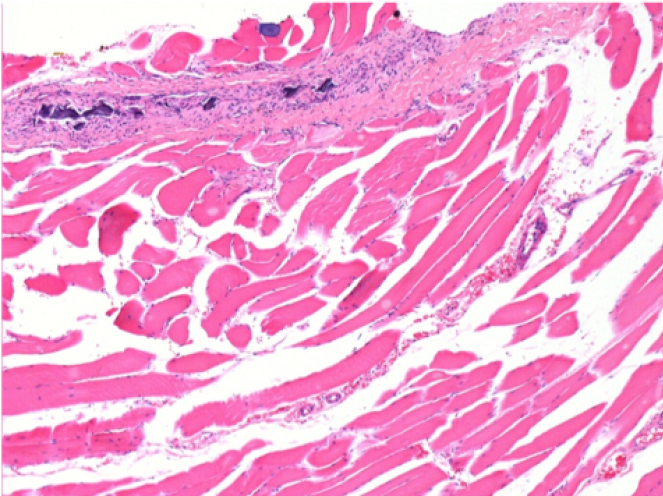

0,5 мл (5x 0,1 мл) підшкірна ін'єкція Ендопіл в праву підшкірну претибіальну ділянку.

Л:200x-Контроль-ПШ

П-10днів-ПШ-200X